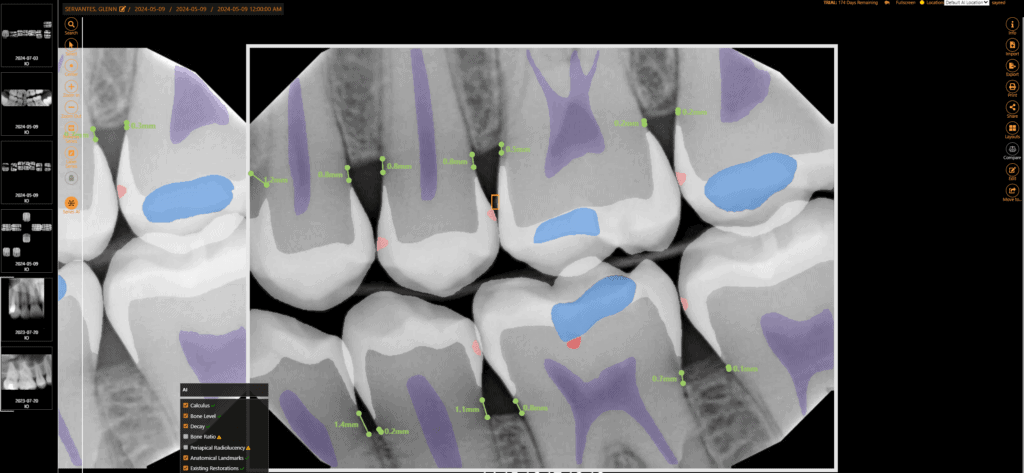

Embedded AI for X-ray Analysis

Leverage advanced AI overlays to improve diagnostic accuracy and consistency for dental professionals and help patients visualize areas of concern. With real-time FDA-cleared AI analysis, share more “a ha” moments with patients to increase case acceptance by up to 30% and submit insurance claims with confidence.

Apteryx XVWeb Dental Imaging is an intuitive cloud-based dental imaging software that allows dentists to capture, view, edit, annotate, and send images securely and easily.

Custom clinical filters and image enhancement tools, templates, bitewings & measurement tools to improve diagnostic accuracy.